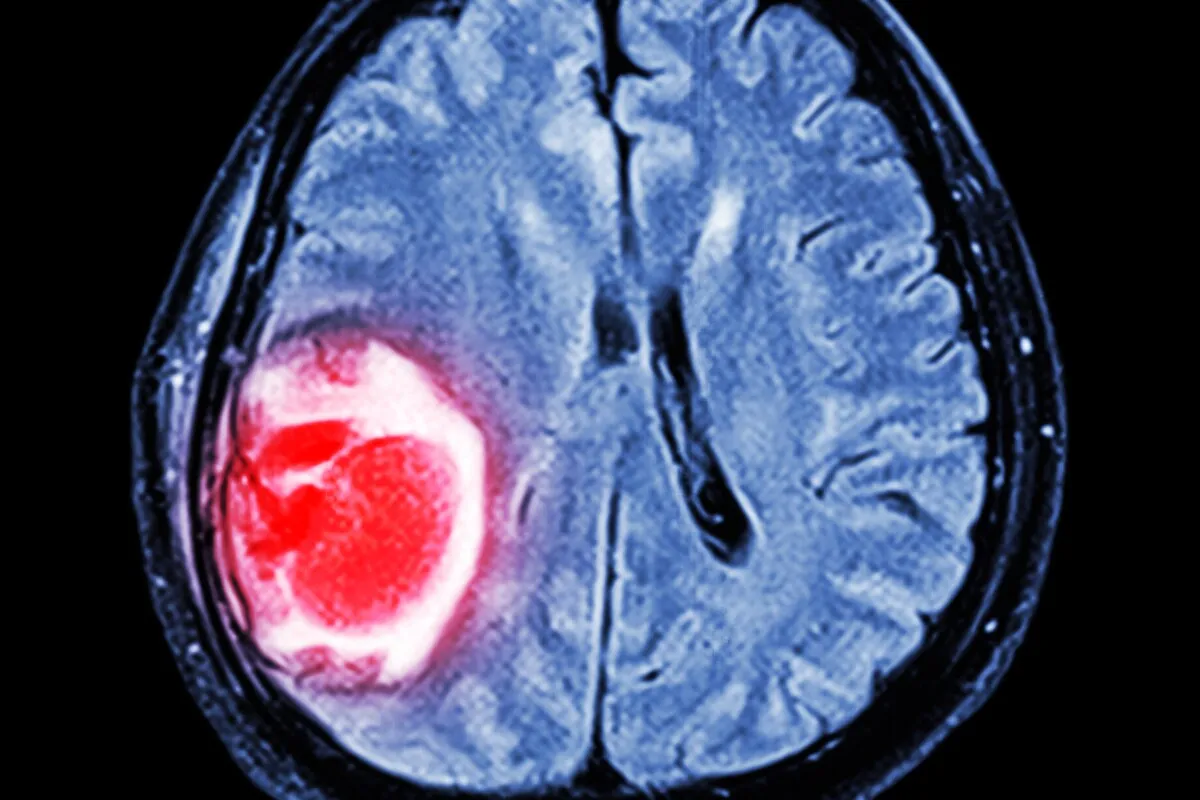

Accurate detection requires highly sophisticated imaging technology and deep neurological expertise. When a patient presents with suspicious cognitive or physical changes specialists immediately order advanced radiological scans to map the cranial cavity.

These scans provide highly detailed three dimensional images revealing the exact location, size and density of the mass. This detailed imaging is absolutely critical for surgical planning and determining whether the growth is pressing against vital functional areas.

Following the imaging phase a tissue biopsy is usually performed to extract a tiny sample of the abnormal cells. Pathologists then examine this tissue under a microscope to confirm the exact diagnosis and assign a severity grade to the condition.